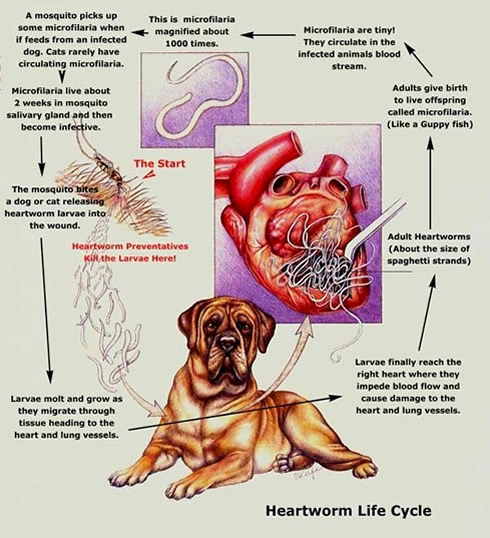

Heartworm is probably one of the least considered worms in our grouping but failure to treat your Pit could ultimately lead to severe heart damage and slow death. Others may be under the impression that it’s just a worm that can be easily treated. In the Heartworm’s case however the best treatment is Prevention. True medical treatment after infection has occurred should be done by a veterinarian, can cause serous side effects including death, and should be expected to be somewhat costly. There are two primary preventative methods used. There is a once a month tablet given your dog or a more recent advancement The Heartworm is a long thin worm, which finds its way to the heart and close by blood vessels. Although Heartworms do not tend to seriously have infected the dog before six months of age. As males and females gather in the heart they mate and reproduce there with the female eventually releasing tiny larvae (microfilariae). As the tiny larvae circulate throughout the infected dog they are once again picked up by their transmitter the mosquito. While in the mosquito they continue developing an then passed onto the next dog not in a preventative treatment program. Once passed back into another dog the larvae begins to mature in the deep tissues of the dog. After maturing to a young adult (approximately 3 months). Once the heart contains both male and females they begin to reproduce after 6-7 months of the dogs initial infection new larvae will be produced. As more and more adults accumulate in the heart they begin to cause heart failure in the dog. The dog will exhibit the same symptoms as heart failure does in that the dog will become tolerant of exercise less and less of exercise and have abdominal fluid buildup. Typically Heartworm diagnosis is done by your vet giving your dog a blood test. These tests are able to predict such infection even before onset of any symptoms. Dogs blood tests should be reviewed annually to insure that any preventative techniques being used is also effective. In order for any dog to be first put on preventative treatment it should be first tested. If an infected dog is treated without having this blood test these treatments can be very harmful and even fatal. A preventative treatment program should typically begin around the dogs 8-10 week of age mark. One way we can all help in controlling the worms is through controlling the mosquito. Here is a basic but effective method of controlling mosquito populations. Eliminate open aired stagnant water sources such as troths, open rain barrels, septic overflow saturation, bird baths, buckets, etc.

There are various types of tapeworm that can affect dogs. The most common is called Dipylidium caninum (the flea tapeworm). The most serious from the human point of view is Echinococcus granulosus (the hydatid tapeworm). Have you noticed the mosquitoes yet? If not hear they come its best to be prepared. Whether you have noticed the mosquitoes or not if your Pit Bull or other pets spend any amount of time outside it’s a good bet that they are aware of their presence. With the presence of Heartworm also come the chance that your pets may be subject to Heartworm infection.

Have you noticed the mosquitoes yet? If not hear they come its best to be prepared. Whether you have noticed the mosquitoes or not if your Pit Bull or other pets spend any amount of time outside it’s a good bet that they are aware of their presence. With the presence of Heartworm also come the chance that your pets may be subject to Heartworm infection. the twice a year shot.